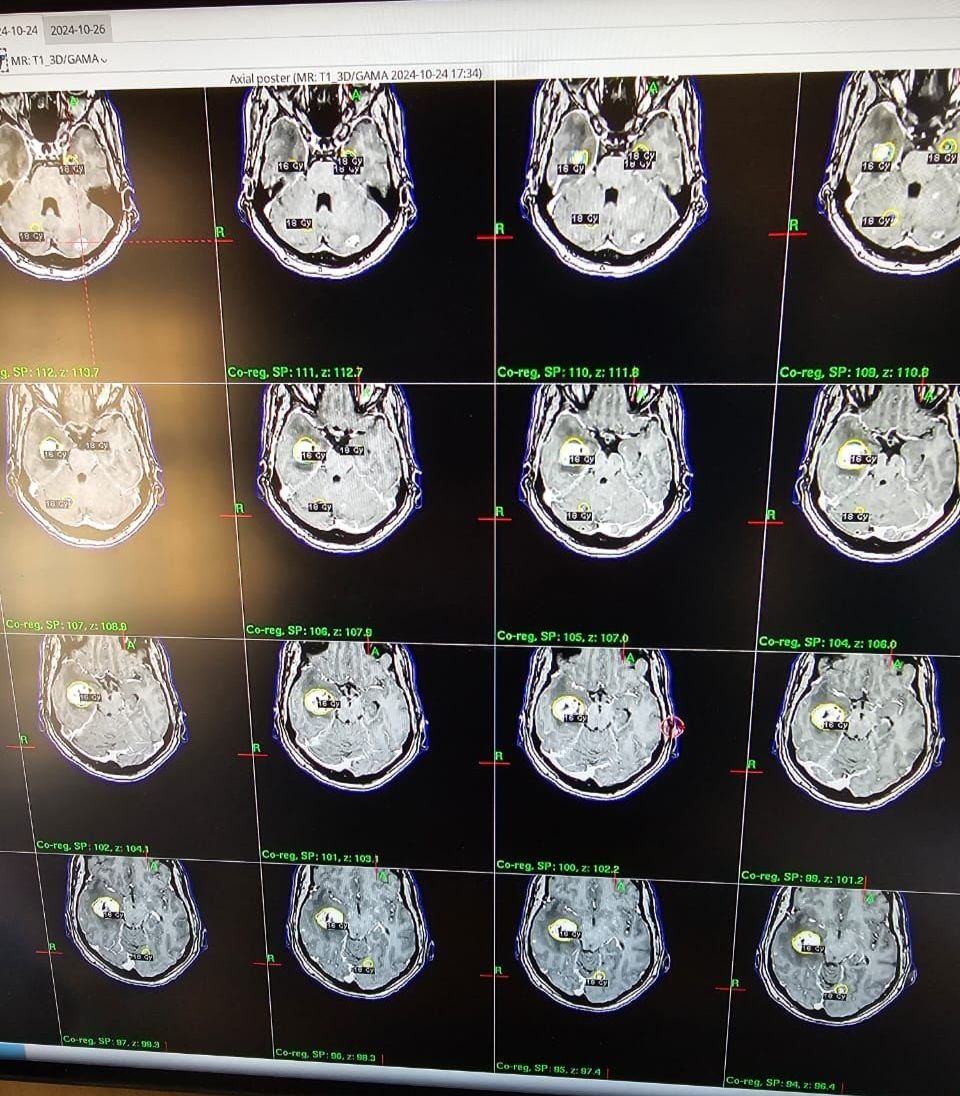

القاء محاضرة من قبل الأستاذ الدكتور عبد الأمير جاسم محمد الخفاجي الى طلاب البورد العراقي في عمليات الكامانايف

قسم الجراحة